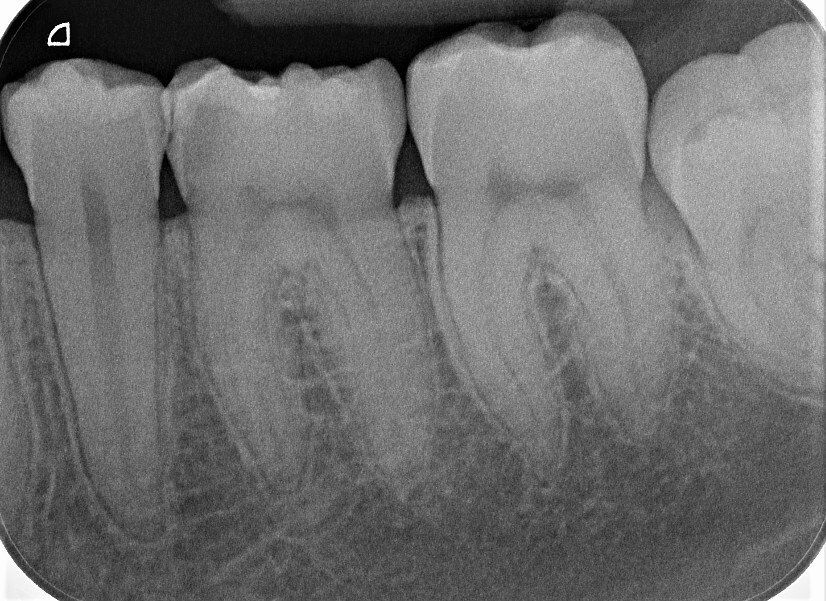

Das Bild links zeigt die Röntgenaufnahme einiger Seitenzähne einer jungen Patientin. Sie klagt über gelegentliche ziehende Schmerzen bei süßen Speisen in diesem Bereich. Im Mund fällt ein Zahn auf, der eine verdächtige Verfärbung im Zahnzwischenraum aufweist, allerdings auch sonst einen verfärbten Zahnschmelz hat. Mit der Sonde kann ich kein Loch ertasten, da die Zähne an dieser Stelle zu dicht aneinander stehen. Wenn ich warten würde, bis die Karies erst voran geschritten und "eindeutig" sichtbar ist, verschlechtert sich die Situation der Patienten. Wenn ich bohre, obwohl es nur eine harmlose Schmelzverfärbung ist, beschädige ich unnötig den Zahn. Ich brauche also mehr Informationen.

>>> Karies oder nicht? Bohren oder belassen? <<<

Das Röntgenbild zeigt eindeutig: Es liegt eine Karies vor, die vom Zwischenraum des sechsten Backenzahnes ausgehend das Zahnbein unterhöhlt. Haben Sie sie auch gesehen?